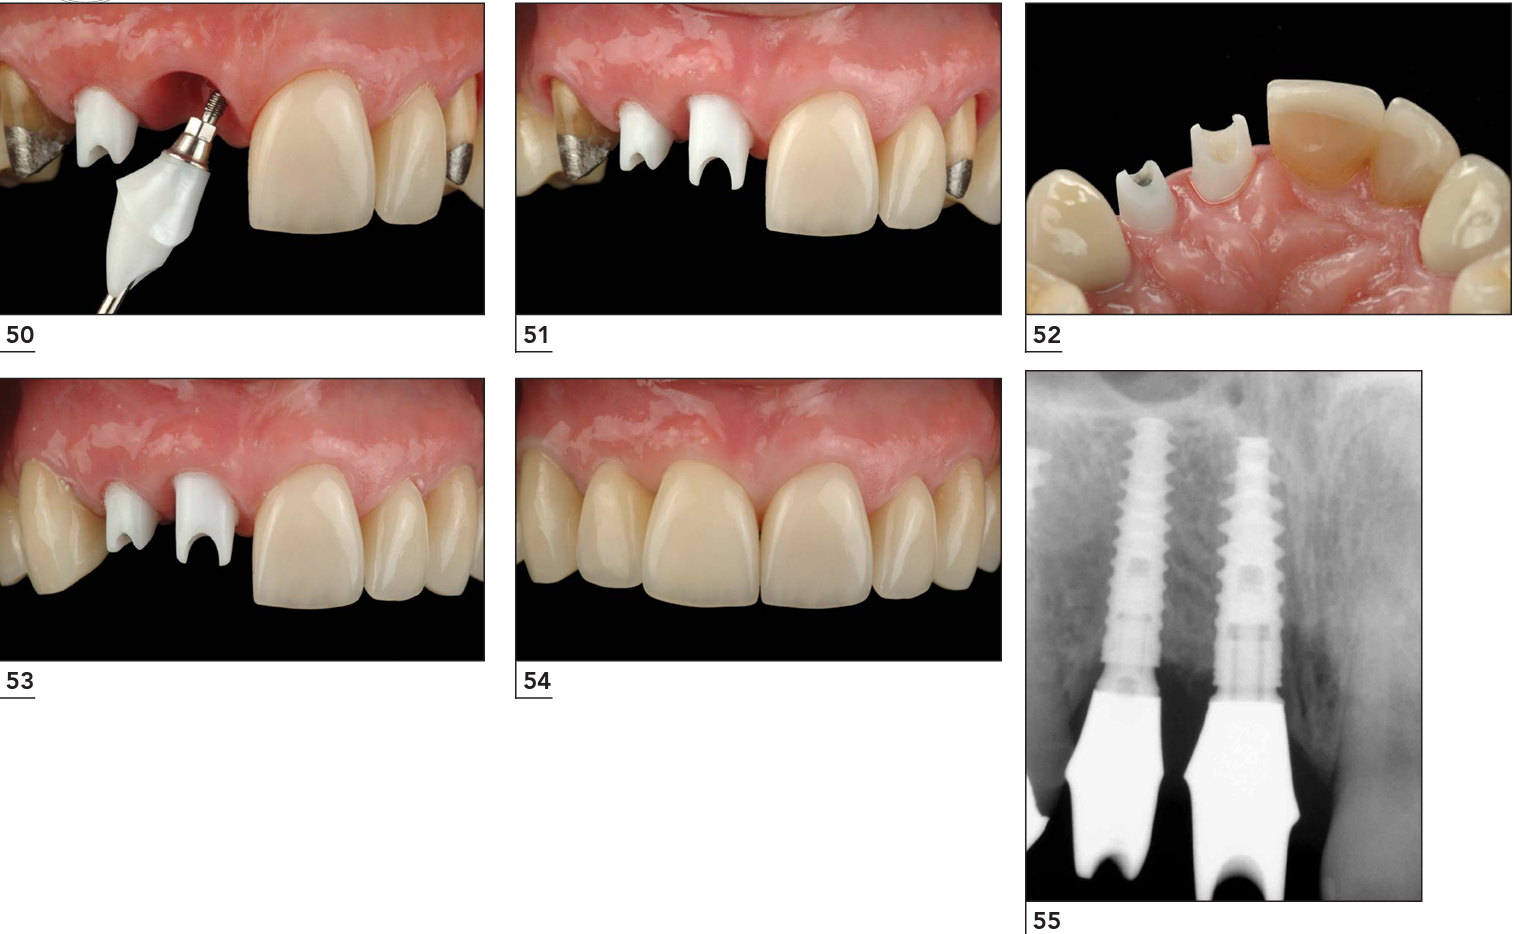

Một ca Implant được lập kế hoạch tốt ngay từ đầu sẽ giảm đáng kể khả năng phải “sửa chữa” về sau.

Một trường hợp được thực hiện thành công bằng giải pháp trồng răng cá nhân hóa tại Lạc Việt Intech.